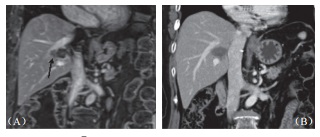

图2 62 岁男性肝癌病患在接受手术及射频消融后于总胆管及门脉旁复发,(A)3cm×2.8cm 大小肿瘤(箭头处)直接贴近肝门;B)消融后6个月肿瘤消失,消融区缩小明显,邻近胆管无扩张

平均整体存活期为22个月(14~32 个月),2个病人在术后第6及第9个月发现局部复发(6.2%),2个病人在第9及第18个月于肝内他处出现复发(6.2%),这4个病人均接受后续射频消融治疗成功,所有病患无恶化存活期为 20.8 个月(14~32个月)。

本研究中所治疗之肿瘤均贴近血管,随访期间也未见血管狭窄或栓塞(图3),影像上也未见受波及胆管进一步扩张或狭窄,只有一位在第9个月出现局部复发的病患,出现轻微胆管扩张,但无胆红素上升之异常。在12个贴近胆囊及15个贴近肠胃壁的肿瘤消融之后,仅有一位(8.3%)在术后超声中出现无症状的胆囊壁水肿,而在1个月后改善,无任何肠胃道受损或消化受影响的迹象。两人术前曾放置胆管内塑料质支架,术后移除时经检视支架无损伤,移除后也不再黄疸。